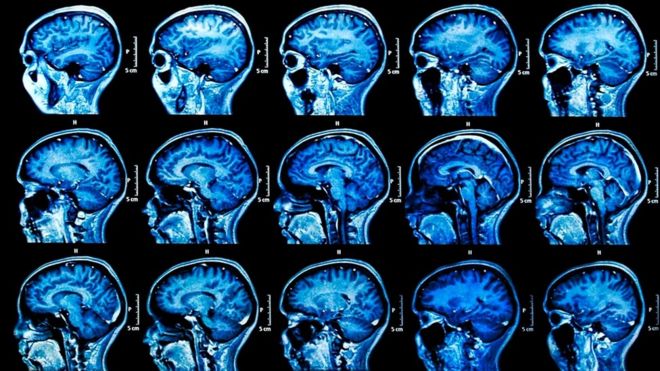

Тот самый вирус, который вызывает простуду на губах, судя по всему, наносит и долговременный урон головному мозгу человека. Это открытие может предложить новые способы лечения старческого слабоумия, пишет Рут Ицхаки в своей статье на сайте Conversation, которую мы перепечатываем.

Более 30 млн человек по всему миру страдают болезнью Альцгеймера, наиболее распространенной формой деменции. К сожалению, это заболевание не лечится, есть только лекарства, которые способны облегчить его симптомы.

Вирус, причастный к болезни Альцгеймера, ВПГ-1, вирус простого герпеса первого типа, известен давно. Большинство детей заражается им в раннем детстве, и затем он остается доминантным в периферической нервной системе (часть нервной системы, находящаяся за пределами головного и спинного мозга).

В 1991 году мы обнаружили, что у многих пожилых людей ВПГ-1 присутствует также в головном мозге. А в 1997 году нам удалось продемонстрировать, что возникает серьезный риск заболевания Альцгеймером, если вирус присутствует в мозге людей, обладающих геном, известным как APOE4.

Мы считаем, что ВПГ-1 - главный фактор, способствующий заболеванию Альцгеймером. Он проникает в мозг пожилых людей по мере того, как их иммунная система с возрастом слабеет.